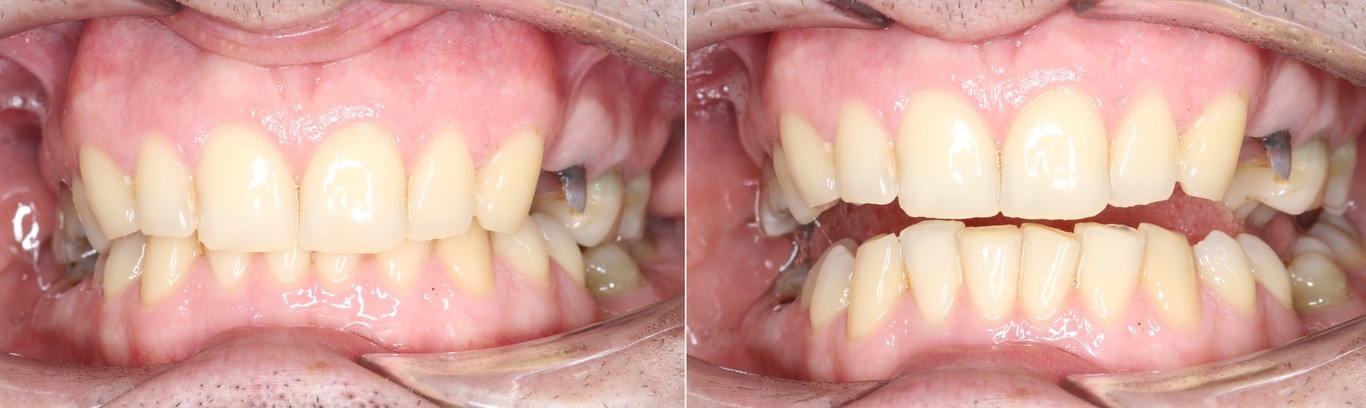

Было:

Стало: